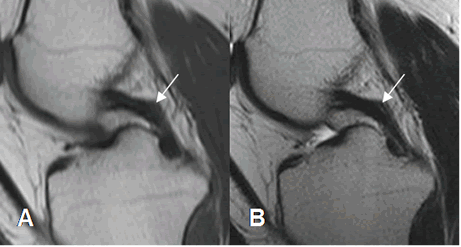

El LCP también se aprecia como una banda hipointensa en todas las secuencias. (2). (Fig 17). El ángulo entre los ejes de la inserción tibial y femoral, normalmente mide 123º. (11).

Este ligamento está rodeado por los ligamentos meniscofemorales que se originan del cóndilo femoral interno y se insertan en el menisco externo. Son el anterior o de Humphrey y el posterior o de Wrisberg. Estas estructuras no deben confundirse con cuerpos libres intra-articulares. (2). (Fig 18 y 19).

Fig 17. LCP normal.

A: RM sagital en T1 y B: RM sagital en T2. Ligamento normal, hipointenso en todas las secuencias.

Fig 18. Ligamentos meniscofemorales.

A y B: RM sagital en T1. Ligamento meniscofemoral anterior (Flecha delgada) y posterior (Flecha gruesa).